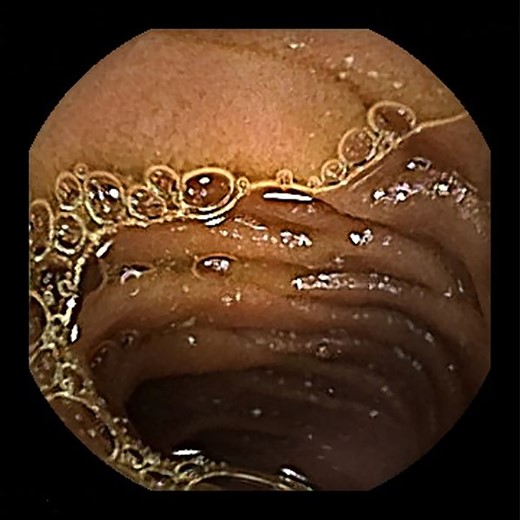

Contrast-enhanced computed tomography revealed a giant irregular mass (45 × 35 mm) in the abdominal wall (Fig. 2). No other intra-abdominal neoplasm were present; however, an irregular lung mass measuring 50 mm in size in the S10 region of the right lobe and a mass measuring 12 mm in size in the S1/2 region of the left lobe were found (Fig. 3). Total gastrointestinal endoscopy, including capsule endoscopy, revealed no neoplasm in the intestinal tract (Fig. 4a–c).